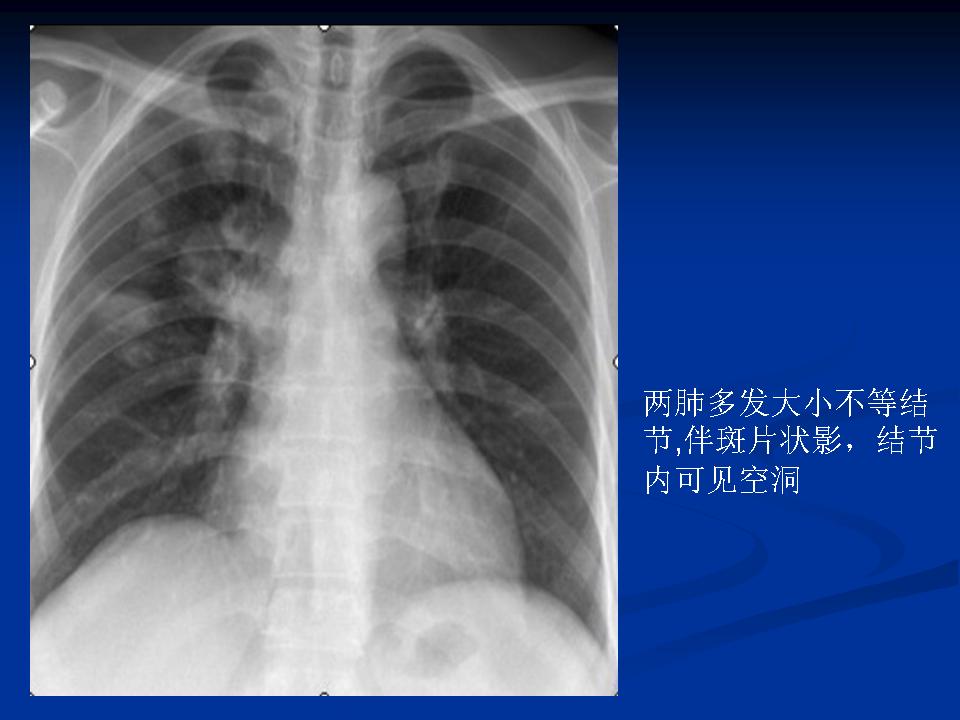

肺转移瘤与韦格肉芽肿影像鉴别